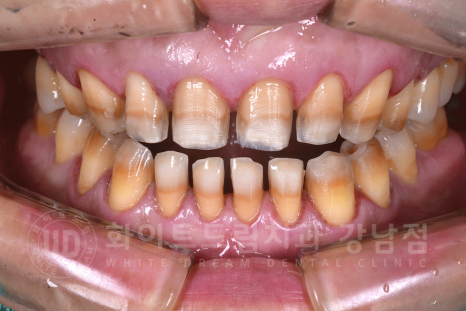

치료 전, 환자분 치아 상태.

- 어금니(37,17,16번 치아)는 현재 본원에서 UV 임플란트 치료 중입니다. ^^

강남역 인근 치과, 테트라사이클린 변색 치료 전

테트라사이클린 변색은 일반 누렁 니와 다르게 심하게 눈에 띄기에 치아 스트레스가 심하신 분들이 많습니다.

오늘 소개해 드릴 환자분도 40대의 남성분이셨는데요.

치아 변색을 한참 고민을 하다가 치료를 받기로 결심을 하신 분이었습니다.

동일 인물이며, 동일 환경에서 촬영되었습니다.

(치료 기간 : 23.12.11 - 23.12.18)

환자분은 14 - 24 / 34 - 44까지의 총 8개의 치아를 라미네이트로 진행하셨습니다.